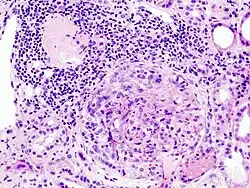

| Histopathological image of crescentic glomerulonephritis in a patient with MPO-ANCA positive rapid progressive glomerulonephritis. Hematoxylin & eosin stain. | |